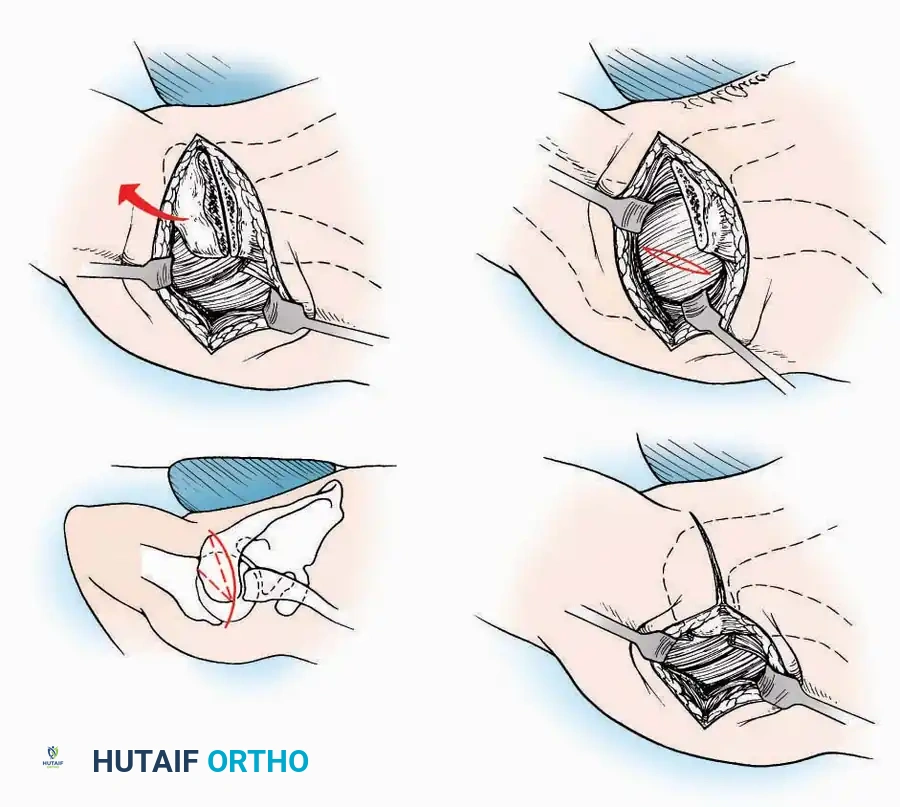

SURGICAL APPROACHES TO THE CALCANEUS

Approaches to the calcaneus are dictated by the pathology—trauma (intra-articular fractures) versus tumor/infection. Positioning is critical; while the prone position offers excellent bilateral access, the lateral decubitus or modified supine positions are more frequently utilized for unilateral trauma.

Lateral Approach (Extensile Lateral)

This is the workhorse approach for open reduction and internal fixation (ORIF) of displaced intra-articular calcaneal fractures.

Indications: ORIF of calcaneus fractures, lateral wall exostectomy, subtalar arthrodesis.

Positioning: Lateral decubitus with the operative leg up, or supine with a large bump under the ipsilateral hip to internally rotate the leg.

Surgical Technique:

* Incision: Begin the incision on the lateral margin of the Achilles tendon near its insertion. Extend it distally to a point 4 cm inferior and 2.5 cm anterior to the lateral malleolus. (For trauma, a classic L-shaped extensile incision is often used, dropping straight down anterior to the Achilles, then curving gently toward the base of the 5th metatarsal).

* Superficial Dissection: Divide the superficial and deep fasciae. It is imperative to create a "full-thickness" flap containing skin, subcutaneous fat, and periosteum to prevent flap necrosis.

* Nerve Protection: The sural nerve crosses the proximal and distal limbs of this approach. It must be identified and protected within the anterior flap.

* Deep Dissection: Isolate the peroneal tendons (longus and brevis). Incise and elevate the periosteum below the tendons to expose the lateral wall of the calcaneus.

* Tendon Management: If severe deformity or infection is present, the peroneal tendons may be divided via Z-plasty and repaired at the conclusion of the case, though this is rarely necessary in modern fracture care.

Medial Approach

Indications: Fixation of sustentaculum tali fractures, medial process fractures, or excision of medial tarsal coalitions.

Positioning: Supine with the hip externally rotated and knee flexed (figure-of-four position).

Surgical Technique:

* Incision: Begin 2.5 cm anterior and 4 cm inferior to the medial malleolus. Carry it posteriorly along the medial surface of the foot toward the Achilles tendon.

* Superficial Dissection: Divide the fat and fascia to define the inferior margin of the abductor hallucis muscle.

* Deep Dissection: Mobilize the abductor hallucis muscle belly and retract it dorsally to expose the medial and inferomedial aspects of the calcaneal body.

* Plantar Exposure: Continue distally by dividing the plantar aponeurosis and the muscular attachments to the calcaneus, or strip them subperiosteally with an osteotome.

* Neurovascular Warning: Meticulously identify and protect the medial calcaneal nerve and the nerve to the abductor digiti minimi (first branch of the lateral plantar nerve), which are highly vulnerable during inferior retraction.

U Approach

Indications: Extensive plantar fasciotomy, radical tumor resection, or complex osteomyelitis debridement requiring access to the entire plantar surface of the calcaneus.

Positioning: Prone, with the leg supported on a large sandbag.

Surgical Technique:

* Incision: Join the medial and lateral approaches described above to form a large, continuous U-shaped incision around the posterior four-fifths of the calcaneus.

* Flap Elevation: Deepen the incision directly to bone. Elevate a massive plantar flap consisting of skin, the specialized fatty heel pad, and the plantar fascia. Retract this flap distally to expose the entire plantar calcaneal tuberosity.

Kocher Approach (Curved L)

Indications: Complete excision of the calcaneus (calcanectomy) for malignant tumors or recalcitrant osteomyelitis.

Surgical Technique:

* Incision: Incise the skin over the medial border of the Achilles tendon, starting 7.5 cm proximal to the calcaneal tuberosity. Extend it distally to the inferoposterior aspect of the tuberosity, curve it transversely around the posterior heel, and continue distally along the lateral surface of the foot to the tuberosity of the fifth metatarsal.

* Deep Dissection: Divide the Achilles tendon directly at its insertion and carry the dissection down to the bone.

* Enucleation: To reach the superior surface, free all tissues beneath the severed Achilles tendon. The calcaneus can then be enucleated subperiosteally or extraperiosteally depending on the oncologic or infectious margins required.